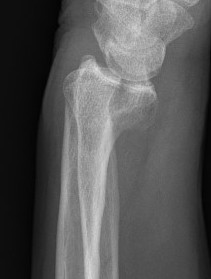

Specific fracture patterns

Volar Barton's

Definition

Intra-articular fractures of the dorsal articular margin of the distal radius

Unstable and allow volar subluxation of the carpus

Management

Volar locking plate

Volar buttress plate without distal screws

Dorsal / Reverse Barton's

Fractures of the dorsal articular margin of the distal radius

Dorsal radiocarpal subluxation if the volar ligament / capsule are disrupted

Dorsal buttress plates

Radial styloid fractures / Chauffeur's Fracture

Associations

Perilunate fracture / dislocations

Radiocarpal dislocation

Scaphoid fractures